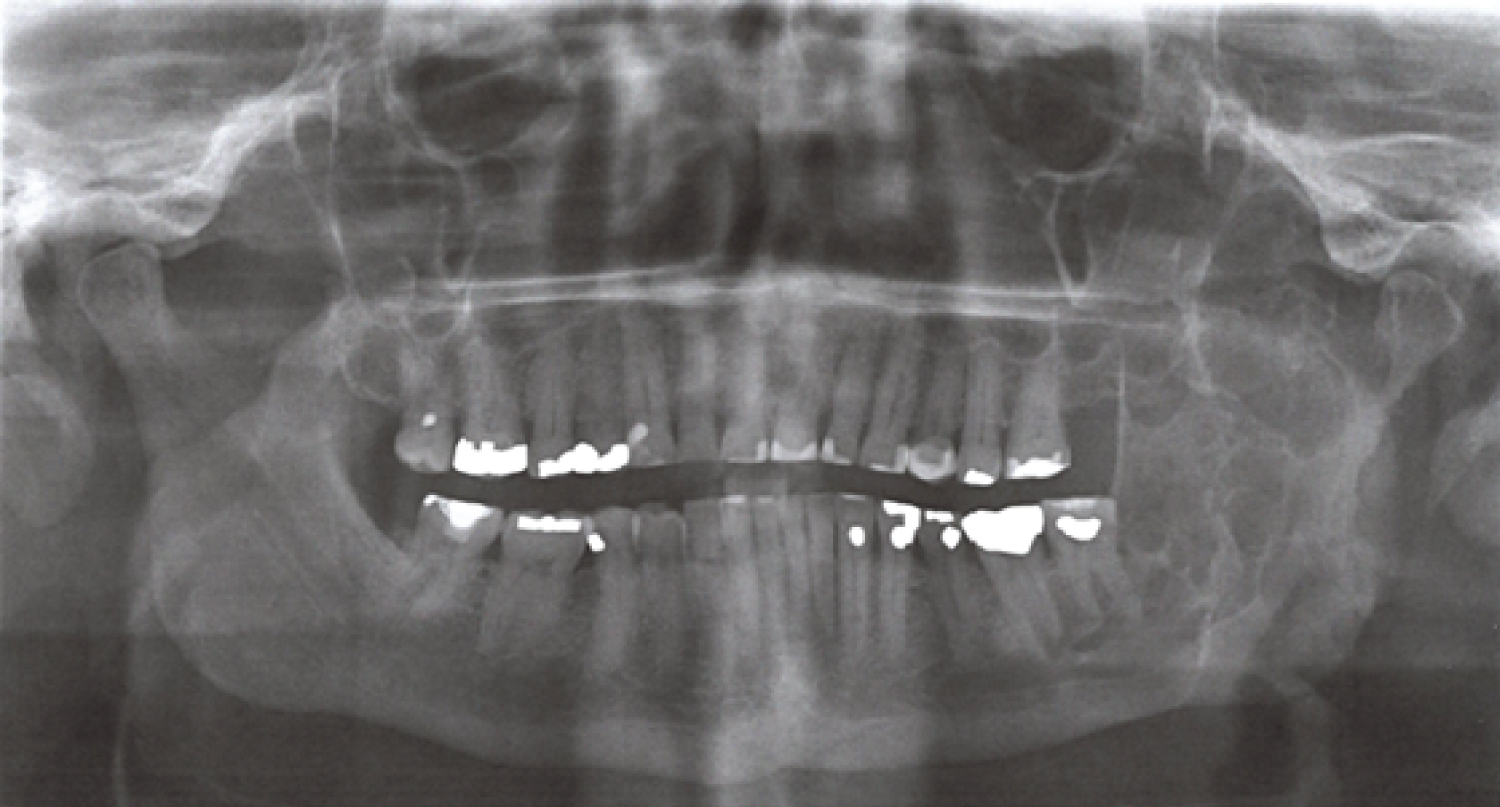

Orthopantomogram (OPG) showed a multilocular radiolucency expansile lesion of the left mandibular body to condylar region (Figure 1).

Figure 1: Panoramic radiographic view demonstrating multilocular radiolucency expansile lesion left mandible. View Figure 1